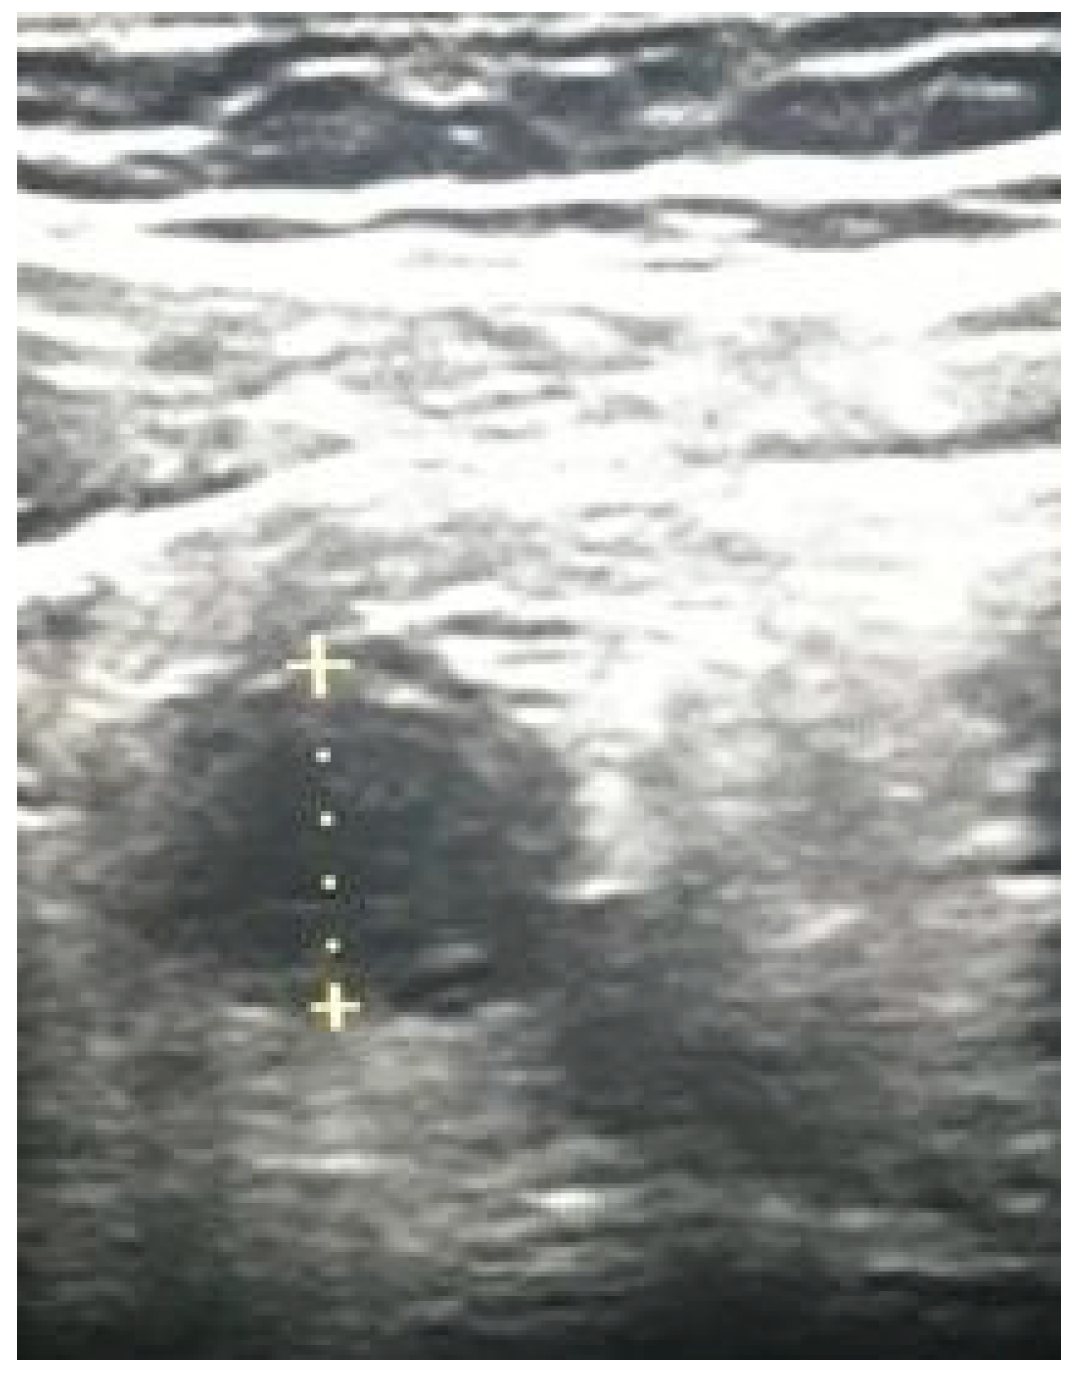

9. Appendicitis